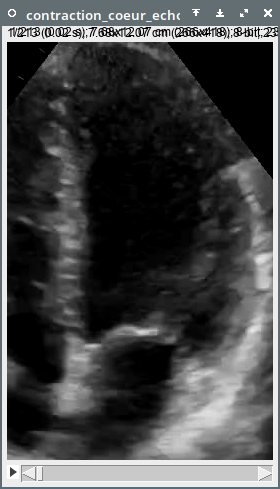

Other uses Echocardiography [map] [map]